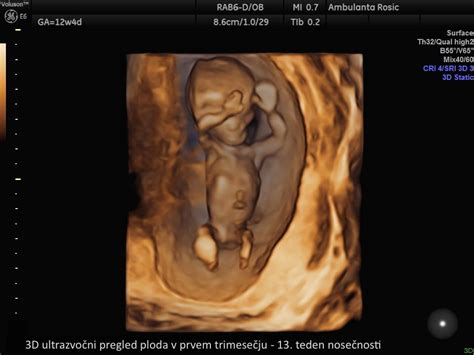

- 3D ultrazvok: Ta tehnika predstavlja tridimenzionalno računalniško rekonstrukcijo slike. Omogoča staršem, da vidijo otrokov obraz in telo v treh dimenzijah, kar je pogosto zelo čustveno doživetje.

- 4D ultrazvok: Pri 4D ultrazvoku je dodana še časovna komponenta. Vidimo lahko, kako se plod v realnem času premika, obrača, zeha ali celo sesa palček. Ta tehnika je še posebej zanimiva za opazovanje vedenjskih vzorcev ploda.

3D/4D ultrazvočne preglede lahko opravimo kadarkoli v nosečnosti, vendar se najpogosteje svetuje pregled med 18. in 32. tednom nosečnosti, idealno med 26. in 28. tednom, ko so obrazne strukture že dobro razvite. Ti pregledi niso obvezen del standardne nosečniške oskrbe, vendar lahko nudijo dragocene vpoglede v razvoj ploda in krepijo čustveno povezavo med starši in nerojenim otrokom. Zdravnik lahko med temi pregledi oceni tudi morebitne obrazne ali druge nepravilnosti pri plodu.